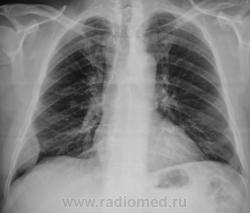

Контроль после флюолрографии.  Мезотелиома или что-то другое?

А не м.б. осумкованный плеврит? Хотя м.б. и мезотелиома ....- сомнения может разрешить КТ

Скорее деструкция 6 ребра с мягкотканным компонентом

Да, деструкция ребра видна хорошо, да и сиротские фрагменты (костные) тоже. "Мягкотканный компонент", прямо богатейший.

Томограммы не делали. По прямому снимку стало ясно все, по крайней мере  - онкология. Пациента сразу же направили ООД. Татьяна Валентиновна права - биопсия решит все, да, и взять не трудно.

Встречал такие ребра около 30 раз в жизни, в приблизительно 25-26 метастазы, остальное - миелома, с первичными опухолями ребер сталкиваться не приходилось...

В течение последних трех или четырех лет уже не помню, мы каждый раз описывали "скиалогию" с определенными рекомендациями, но нашим коллегам клиницистам, все это было,  до аж самисенькой с...., то им было некогда, то пациент выбрыки - "не хочу", "не буду"...

Изначально "процессик" был весьма малюсеньким.

Справедливости ради, скажу, что в первом протоколе, как заключение, я написал мезотелиому. После работы пересматривая отобранные на флешку случаи, я как-то усомнился, завел "ровер" и поехал поколдовать на "сиаре", убедился, что не все так просто, как мне показалось сначала, да, и томограмм, которые, я так полюбляю не было.

Конечно...трехлетний анамнез несколько меняет дело...но и не в пользу метастаза...отнюдь. На каком то этапе произошло озлокачествление (ребро!!!!). Случай очень интересный. Ждем результата.

Гистология - метастаз аденокарциномы. Первичную опухоль не нашли...